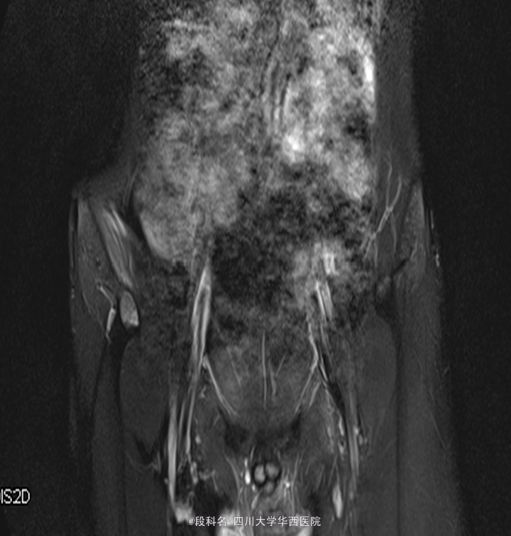

查体:右髋局部无红肿,有压痛,皮温不高,感觉无减退。右侧髋伸屈、外展、内收,因疼痛无法评测。右膝屈曲4级,伸膝3级,踝背伸、跖屈4级 。左侧肌力正常,肌张力正常。右侧直腿抬高试验40°(+),加强实验(+),右侧4字实验(+)。辅助检查:当地医院CT检查示:L4/5椎间盘轻度膨出,L5/S1椎间盘轻度突出,建议MRI检查。我院血常规示:血小板计数 425 10X9/L,白细胞计数 12.26 10^9/L,中性分叶核粒细胞绝对值 8.34 10^9/L。生化示:血沉53.mm/h,C反应蛋白(CRP)42.80mg/L。痰涂片抗酸染色(连续3次):未查见抗酸杆菌。免疫球蛋白A 4050.00 mg/L ↑ 免疫球蛋白M 2240.00 mg/L ↑C-反应蛋白 31.80 mg/L ↑。T细胞亚群正常。CD3细胞亚群 71.40 %CD4细胞亚群 37.00 % CD8细胞亚群 29.80 % CD4/CD8比值 1.24。痰培养示:产酸克雷伯氏菌 混丛,较多。结核抗体检测 阴性 。骨盆MRI示:右侧骶髂关节面骨质见斑片状长T2WI及长T1WI信号,关节间隙模糊、局部狭窄,邻近髂腰肌、梨状肌、臀肌群见斑片状T2WI高信号影。左侧骶髂关节及双侧髋关节未见确切异常。